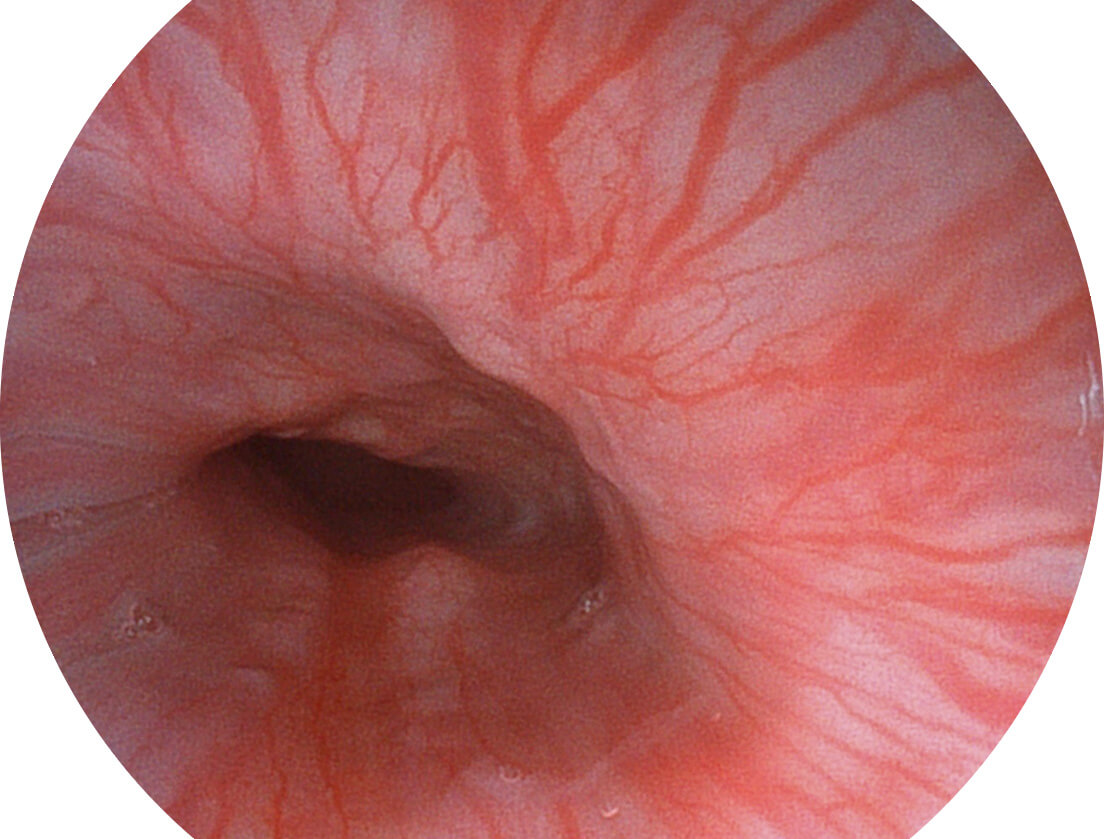

图像具有高亮度、高黏膜血管颜色对比度的特点,且不改变粘液、食物残渣、粪便的基本颜色,可在中远景下进行观察,助力消化道早期疾病的诊断。

• 白光图像 SFI图像